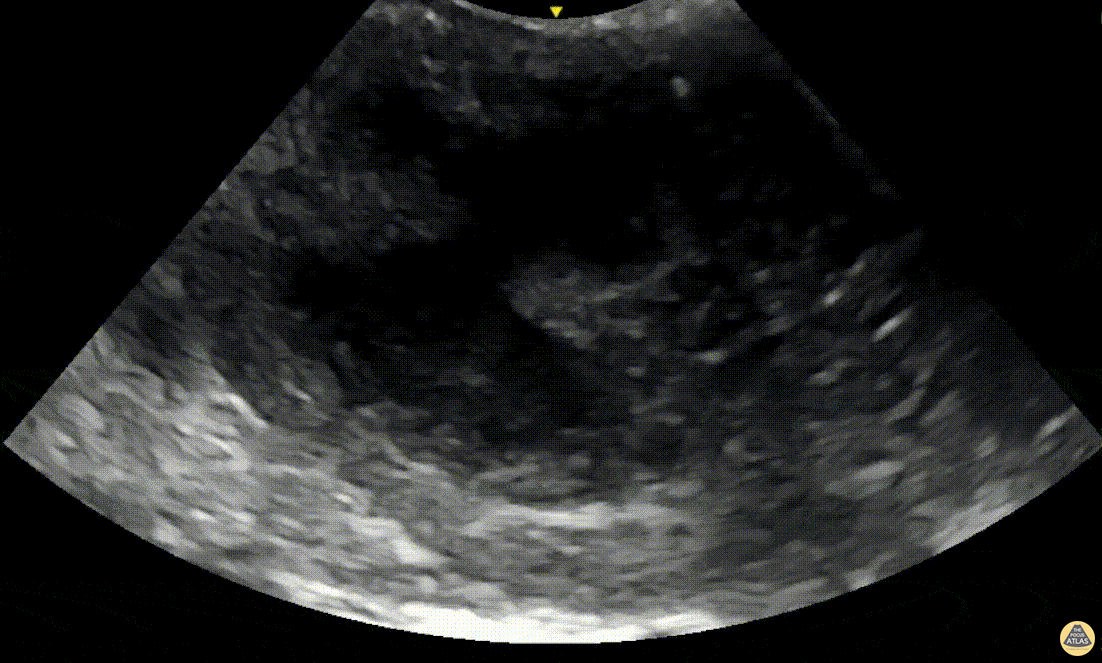

Soft Tissue - Peritonsillar Abscess with Posterior Color Flow

A 24-year-old male presented to the ED with 3 days of fever, headache and sore throat. On exam he was noted to have oropharyngeal erythema with a fluctuant area in the left peritonsillar region. A POCUS was performed of the area using an endocavitary probe, revealing clear circumscribed hypoechoic region without internal color flow. Aspiration of the PTA was performed with moderate purulent drainage. Dr. Elizabeth Hanson, Denver Health Emergency Medicine Alexandra Netto, PA, Denver Health Emergency Department